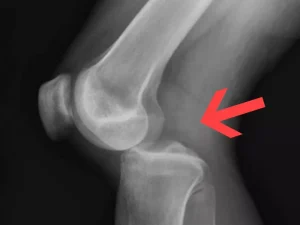

افیوژن زانو

افیوژن زانو چیست؟ راهنمای کامل

افیوژن زانو اصطلاحی است که در پزشکی برای توصیف تجمع